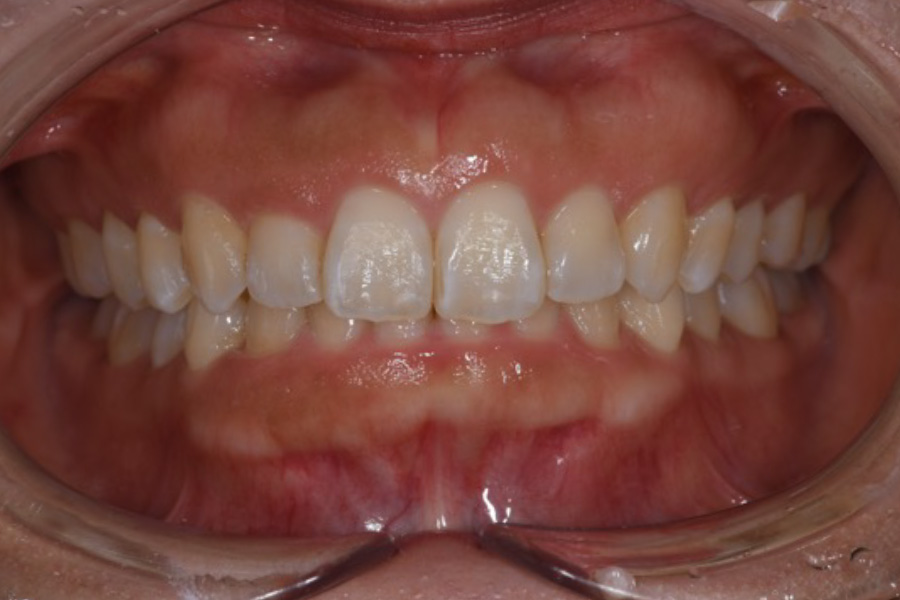

歯を矯正したい

【マウスピース矯正】

- 担当医

- -

- 主訴

- 矯正希望

- 期間

- 5年

- 費用

- マウスピース矯正とプレミアムホワイトニングセット

1,280,340円(税込)

- 治療内容

- 目立ちにくいマウスピース矯正(非抜歯矯正)

歯と歯の間に隙間をつくることにより、歯列弓を広げながら治療を行いました。

また矯正用マウスピースをトレー代わりにし、ジェルを入れてホームホワイトニングを同時に行っております。

- 治療に伴うリスク

- ・後戻りする可能性があるのでリテーナーを最低でも矯正期間以上はつけること

・ホワイトニング後、一時的に痛みが出る場合があります

・稀にほっぺた、唇、舌などに口内炎や傷ができることがあります